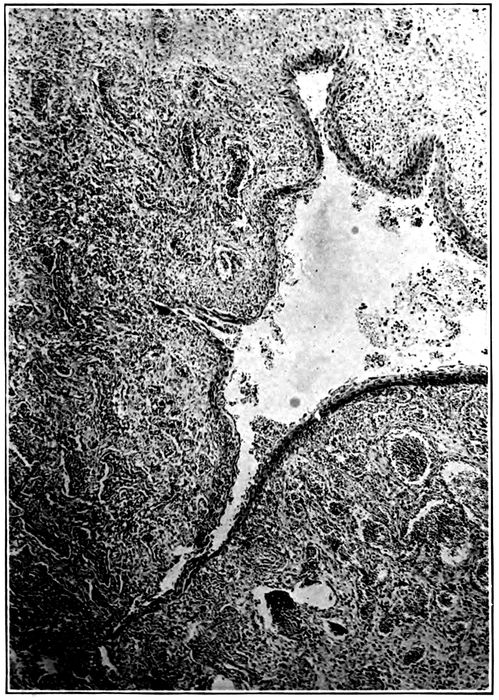

| 10. | Interstitial suppurative pneumonia; interstitial septa are the site of suppuration and lymphatics are distended with purulent fluid; empyema | 211 |

| 11. | Suppurative interstitial pneumonia | 212 |